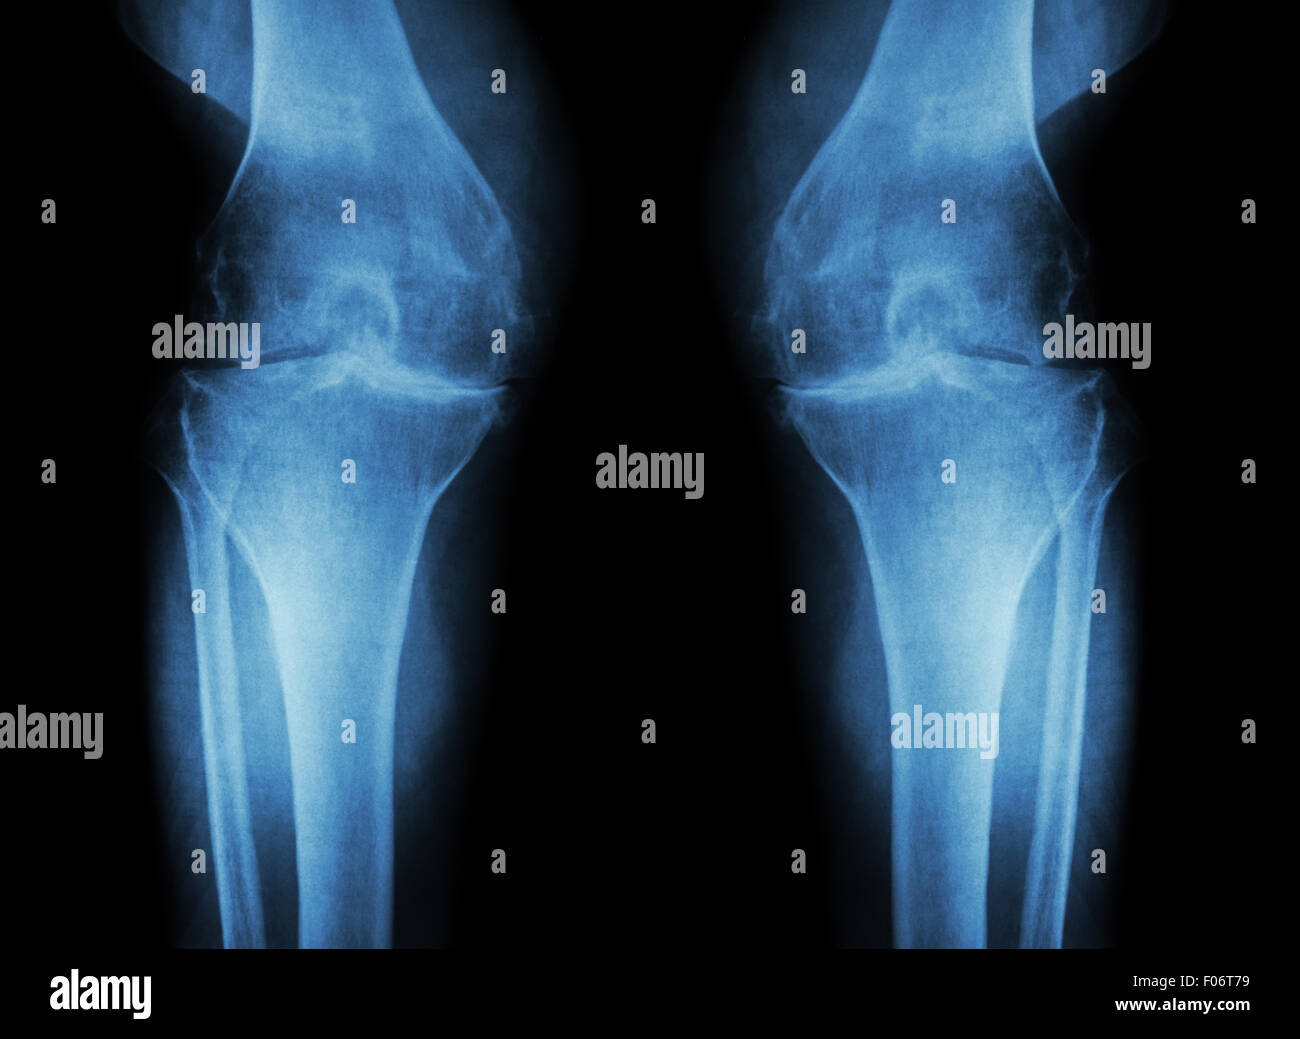

Flim X-ray genou AP : montrer l'articulation du genou humain normal Banque D'Imageshttps://www.alamyimages.fr/image-license-details/?v=1https://www.alamyimages.fr/photo-image-flim-x-ray-genou-ap-montrer-l-articulation-du-genou-humain-normal-77253242.html

Flim X-ray genou AP : montrer l'articulation du genou humain normal Banque D'Imageshttps://www.alamyimages.fr/image-license-details/?v=1https://www.alamyimages.fr/photo-image-flim-x-ray-genou-ap-montrer-l-articulation-du-genou-humain-normal-77253242.htmlRFEDK58A–Flim X-ray genou AP : montrer l'articulation du genou humain normal